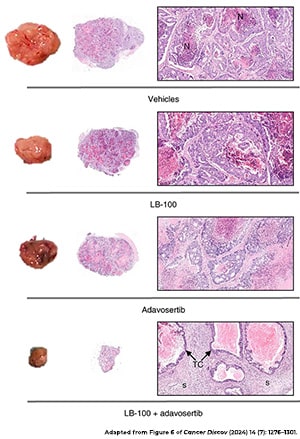

Striking a Deal With the Devil: Activating Oncogenic Signaling for Cancer Treatment

Shutting off cancer-promoting pathways is a common treatment strategy, but in a recent study published in the American Association for Cancer Research (AACR) journal Cancer Discovery, researchers hypothesized that activating these pathways may be an effective approach, too.

Their rationale was that hyperactivation of oncogenic signaling in cancer cells would exacerbate cellular stress and make the cells dependent on stress response pathways. This, they reasoned, would make the cancer cells susceptible to drugs that block stress responses.

They tested their hypothesis in colorectal cancer cell lines, treating the cells with an inhibitor of the tumor suppressor PP2A, which amplified the activation of multiple oncogenic pathways. When PP2A inhibition was combined with an inhibitor of the replication stress response protein WEE1, cancer cells were killed at a higher rate than observed with either inhibitor alone. The combination also exhibited antitumor activity in patient xenograft mouse models of colorectal cancer.

Moreover, the researchers found that when cancer cells became resistant to the combined inhibition of PP2A and WEE1, they did so by shutting off the oncogenic signaling that made them dependent on WEE1—the very signaling that was driving the cancer.

The researchers proposed hyperactivation of oncogenic signaling as a potential therapeutic approach that not only makes cancers vulnerable to WEE1 inhibition but also leads to an acquired resistance phenotype that effectively turns off tumor-driving pathways.